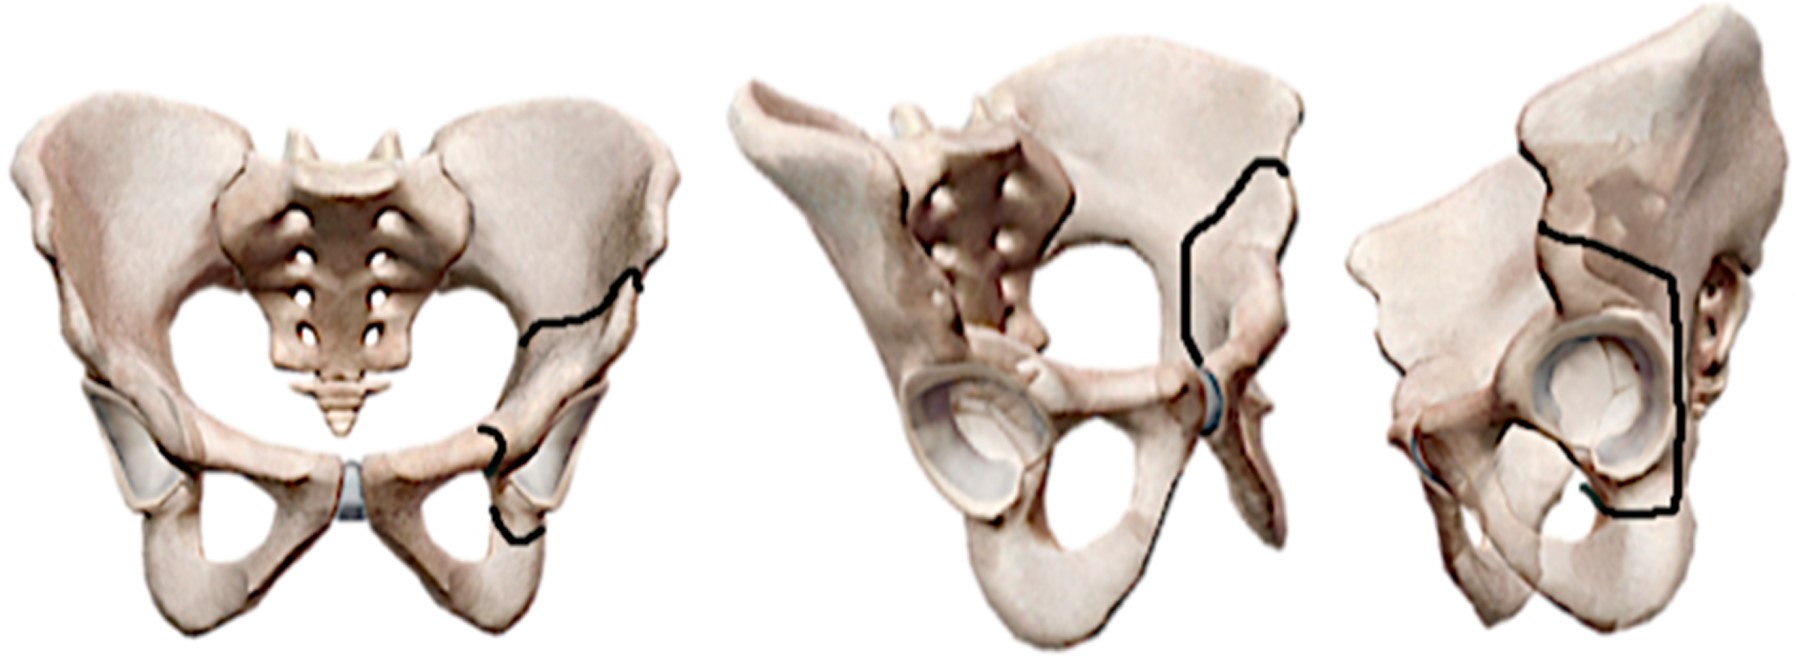

Osteotomías pélvicas

Las osteotomías pélvicas fueron ideadas principalmente para resolver el grave problema de las secuelas de una luxación congénita de la cadera no tratada o insuficientemente tratada. Han sido varios los autores que han contribuido con su experiencia y talento ideando diversos tipos de osteotomías (Figuras 3 y 4). El objetivo de éstas es reorientar el acetábulo en relación con la cabeza femoral, proporcionando cobertura y contención adecuada a la cabeza del fémur.

El pionero del tratamiento con osteotomías pélvicas fue Robert Bruce Salter,24 quien en 1961 hacía un corte de osteotomía supraacetabular en cuña en niños e introducía en ella un injerto óseo autólogo tomado de la cresta ilíaca para mantener la posición del acetábulo reorientado. Se usa como fulcro la sínfisis púbica.

La idea de reorientación acetabular de Salter fue seguida por diversos autores. David Hollingworth Sutherland25 en 1977 modificó la técnica de Salter al agregar al tradicional corte supraacetabular en ilíaco una osteotomía adicional cerca de la sínfisis del pubis. Llamó a esta técnica "doble osteotomía innominada".

Después de la innovación de Sutherland, quien propuso una doble osteotomía, Howard H. Steel26 siguió el mismo principio, pero lo hizo efectuando una triple osteotomía, osteotomizando el ilíaco, el isquion y el pubis separadamente. A esta técnica la llamó "triple osteotomía innominada". Esto ocurrió en 1973 (Figura 5).

Más tarde en 1981, Dietrich Tönnis27 hizo modificaciones a la técnica de triple osteotomía de Steel, proponiendo que los cortes de osteotomía no deben hacerse alejados de la articulación, sino por el contrario, lo más cerca posible. Con esta modificación buscó disminuir la limitante en la movilización del fragmento acetabular, que era ocasionada por los tejidos blandos que actúan como una brida dificultando su movilización, como ocurría con las osteotomías de Sutherland y Steel. La llamó "triple osteotomía yuxtaarticular" (Figura 6).

Desafortunadamente, en las osteotomías anteriores que cortan el hueso innominado en diferentes partes, ya sea cerca o lejos de la articulación, los tejidos blandos que se insertan rodeando el acetábulo actúan como una auténtica correa o brida que limita el grado de corrección deseada y pueden llevar a inestabilidad del fragmento acetabular libre. Otro problema es que irrumpen la columna y muro posterior desfigurando el anillo pélvico. La gran limitante de estas osteotomías (a excepción de las periacetabulares que trataremos más adelante) es que están diseñadas para efectuarse principalmente en niños, ya que éstos tienen los centros de cartílago de crecimiento abiertos en el cartílago trirradiado. Aunque se han intentado en adultos, sus resultados a largo plazo no son los esperados. Basta con mencionar a Peters28 y colaboradores, quienes siguieron a 50 pacientes adultos por un período de nueve años que habían sido osteotomizados con la técnica de Steel y encontraron una tasa de falla de 27%.

En 1955 Karl Chiari29 ideó una osteotomía que tiene un concepto totalmente diferente al resto de las osteotomías existentes en esa época para el tratamiento de la displasia acetabular. El procedimiento consiste en efectuar una osteotomía ilíaca supraacetabular completa, que permita el desplazamiento el fragmento inferior (trasfondo-cabeza) medialmente y el superior lateralmente. Esto produce una disminución del brazo de palanca medial y un aumento en la cobertura a la cabeza femoral por el fragmento ilíaco superior. El resto de la pelvis queda en su lugar de origen (Figura 7). El requisito indispensable es interponer la cápsula articular entre el fragmento superior desplazado y la cabeza femoral, la cual sufriría una metaplasia a fibrocartílago. Aunque desfigura el anillo pélvico, esta osteotomía fue muy popular, ya que técnicamente es muy fácil de hacer; sin embargo, con la aparición de las osteotomías periacetabulares y las prótesis de cadera prácticamente se ha abandonado.

Un hito en el tratamiento de la displasia acetabular en adultos con osteotomías fue el desarrollo de las osteotomías periacetabulares sin irrupción del anillo pélvico; los máximos representantes en este tipo de osteotomías fueron Heins Wagner30 y Reynold Ganz.31

Wagner30 en 1978 contribuyó de manera importante a este concepto con su osteotomía esférica periacetabular. Las osteotomías periacetabulares en general tienen la enorme ventaja de que no irrumpen la columna ni el muro posterior, dejando intacto el anillo pélvico. Por lo anterior, es mucho mejor la estabilidad que se obtiene en el fragmento libre acetabular osteotomizado. Otra ventaja es que se facilita el grado de cobertura de la cabeza femoral, y ya no se tiene la limitación de la movilización del fragmento acetabular al no intervenir de manera importante los tejidos blandos. Por lo anterior, se pueden obtener mucho mejores correcciones.

Sin duda, el que más contribuyó a la idea de las osteotomías periacetabulares fue Reynold Ganz,31 quien describió una osteotomía periacetabular que nombró "osteotomía bernesa" (Figuras 4 y 8). A esta osteotomía se le considera en la actualidad el estándar de oro para corregir las secuelas de las displasias acetabulares. Desafortunadamente, no es de utilidad cuando se aplica en casos avanzados de coxartrosis.